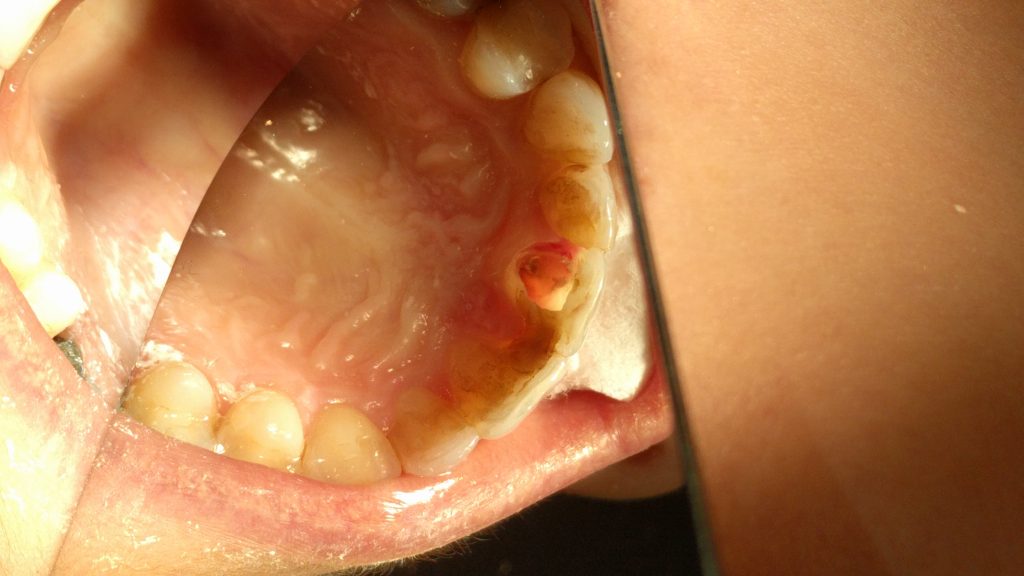

Streszczenie: Artykuł przedstawia etapy leczenia zębów dotkniętych resorpcją zewnętrzną i wewnętrzną. W każdym przypadku do leczenia użyto cementu Activa BioActive, dzięki czemu zęby udało się uratować przed całkowitym usunięciem.

Summary: The article presents the stages of the treatment of teeth affected by periapical and internal resorption. In each case, Activa BioActive cement was used for the treatment, and therefore the teeth were saved from complete extraction.

Każdy z nas w swojej praktyce spotyka się czasami z dość trudnymi przypadkami, do których możemy zaliczyć m.in. głęboką próchnicę korzenia czy silną resorpcję zewnętrzną lub wewnętrzną korzenia. Często podejmowane są decyzje prowadzące do usunięcia takiego zęba i odbudowy braku przy pomocy implantu czy mostu. Wielu pacjentów niestety nie stać na takie rozwiązanie i kończy się to często brakiem uzupełnienia utraconego zęba lub wykonaniem przez technika uzupełnienia protetycznego ruchomego w postaci protezy. W przypadku gdy zęby sąsiednie obok utraconego zęba są mocno zniszczone, założenie mostu wydaje się dobrym rozwiązaniem, gdyż całość pracy protetycznej nie tylko uzupełni brakujący ząb, ale także wzmocni sąsiadujące z luką zęby. Problem [...]